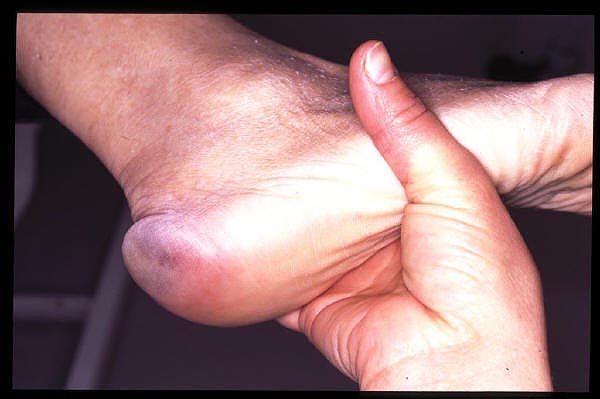

Bursitis primer metatarsiano